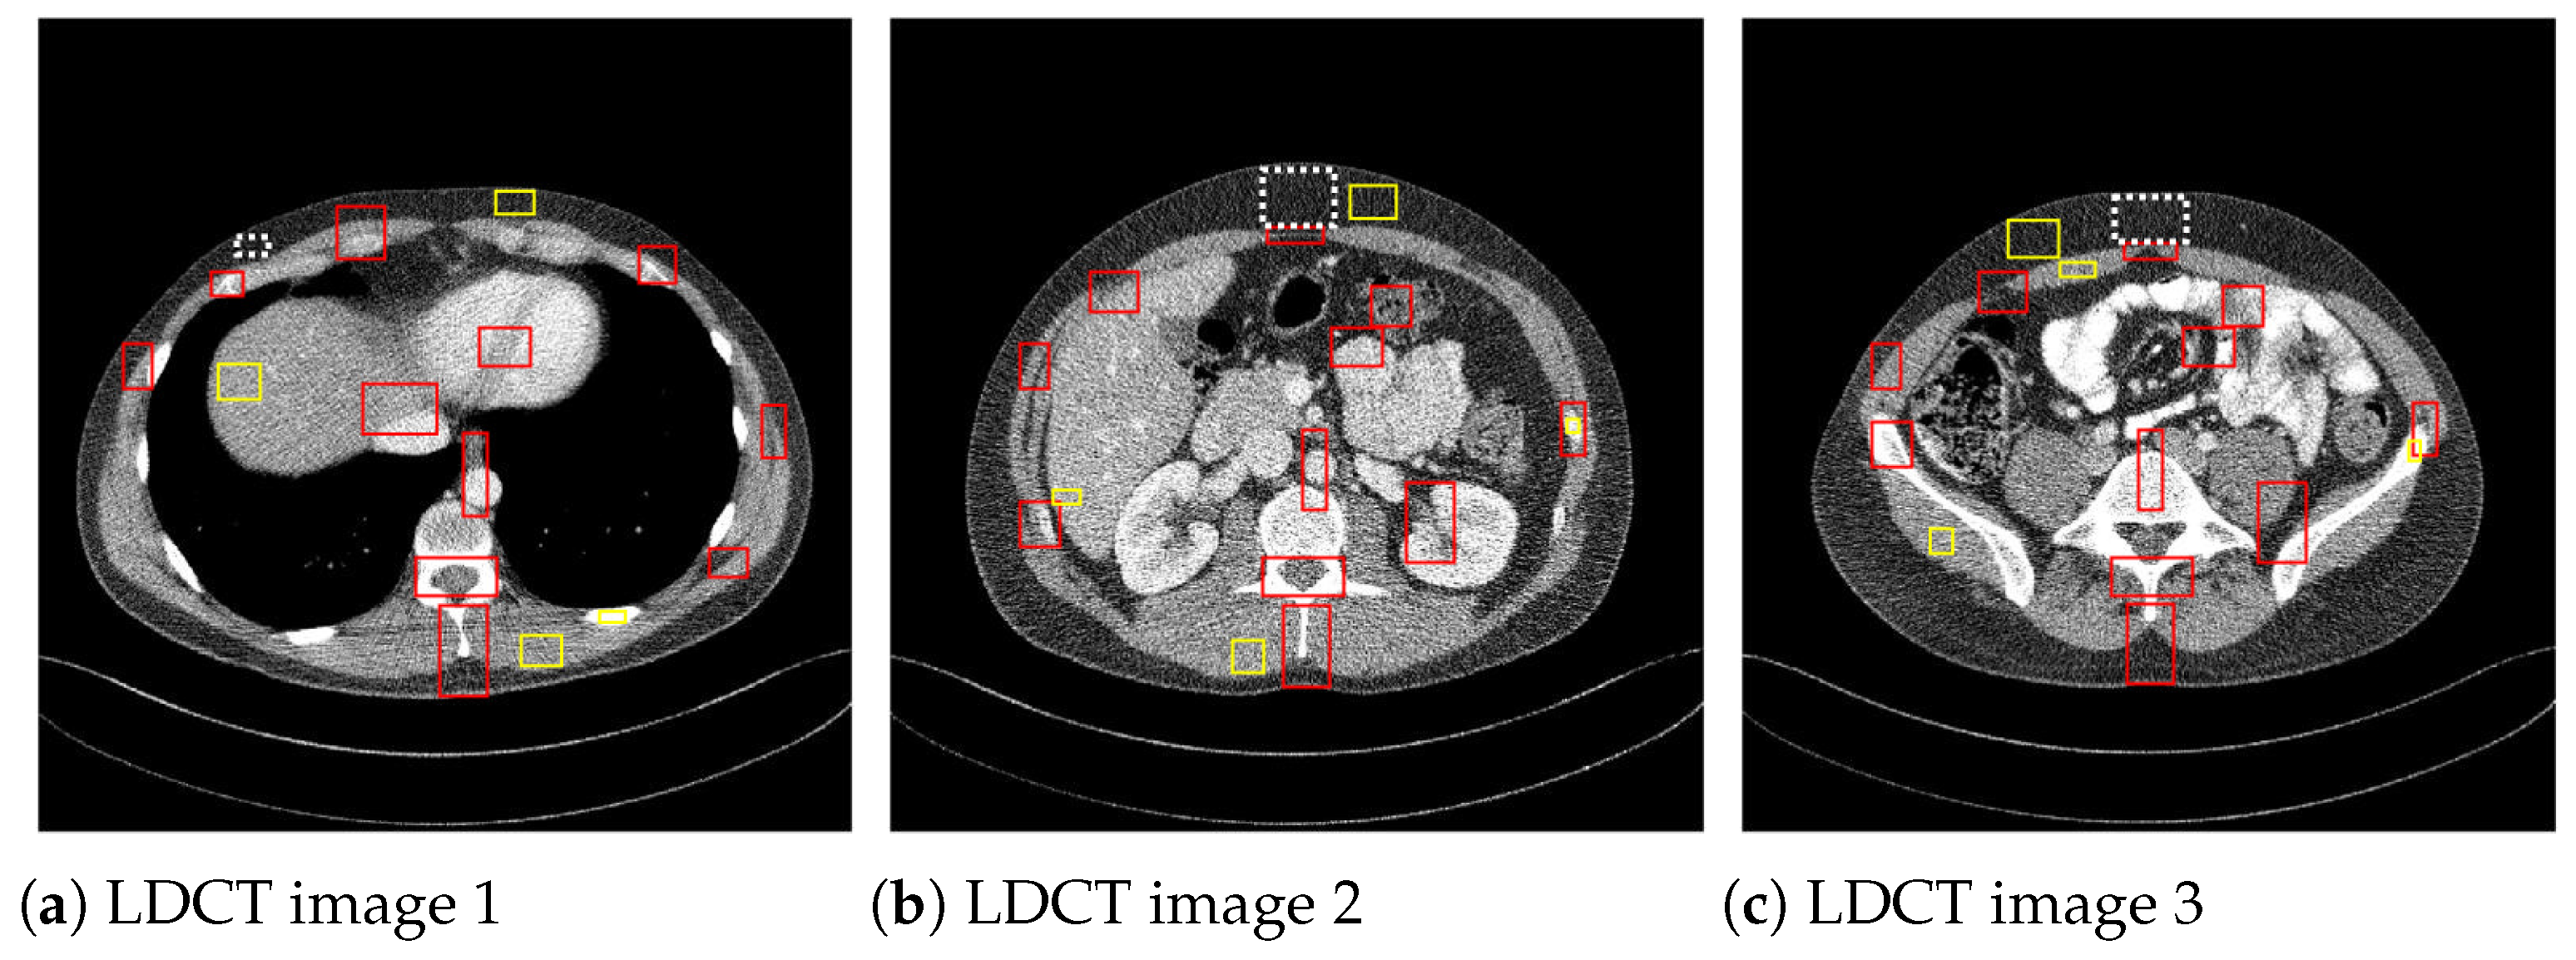

where x i j , η i j , y i j are the pixels of the original, the noisy, and the denoised image, respectively. To analyze the filtering efficiency in the case of the noisy low dose CT images, where there is no noise-free reference image, the image quality metrics used were the signal-to-noise ratio (SNR) [34], the contrast-to-noise ratio (CNR) [34], and the average equivalent number of looks (ENL) [34]. The CNR measures the contrast between an image feature and an area of homogeneous noise, while the ENL measures smoothness in areas that should have a homogeneous appearance but are corrupted by noise. These image quality metrics are defined as:

where I is the matrix of pixel values for the CT image, and σ n 2 is the noise variance computed on a homogeneous region. μ m is the mean of the pixels in the mth region of interest (ROI), σ m is standard deviation, and μ b and σ b are the pixel mean and standard deviation of a homogeneous region of the image, respectively. The CNR values are averaged over the red ROIs shown in Figure 5 and the ENL over the yellow homogeneous ROIs. To compute σ b 2 , the homogenous ROI in Figure 5, delimited by a dashed line, was used.

Figure 5. ROIs considered to compute CNR and ENL measures.